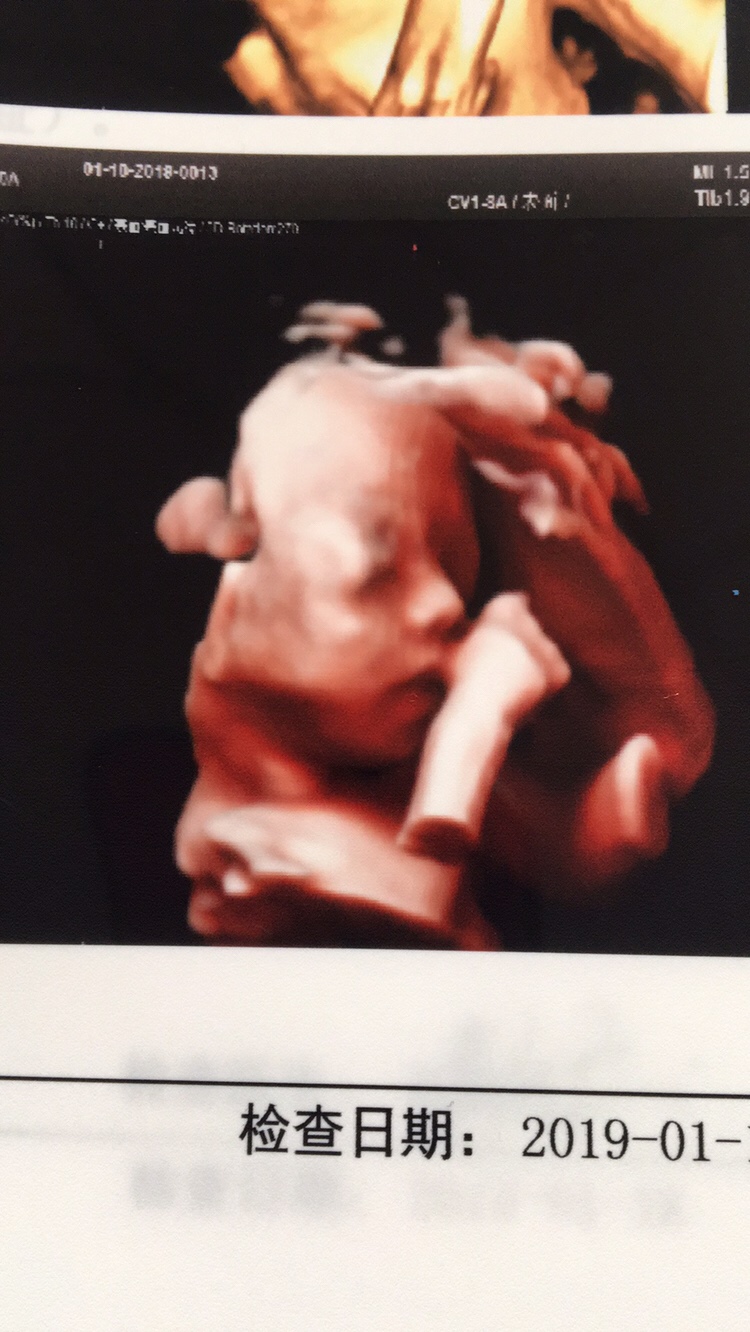

孕24周+4天

好可爱,我家娃一直捂脸,就是不给看

🍃不如吃茶去[帖主]:调皮